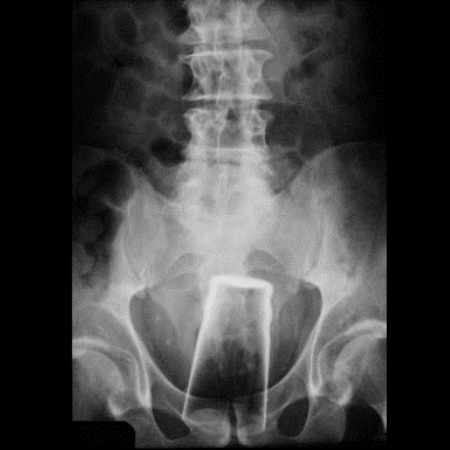

8. A Bottle Had Somehow Appeared In His Groin

A man was forced to seek emergency medical advice when he was complaining of stomach pains. It's no wonder...considering he had a bottle stuck inside him. And, what's more, he tried to fish the bottle out using a fishing wire. He first pretended he had no idea why he had pain until the X-rays were undeniable.Advertisement